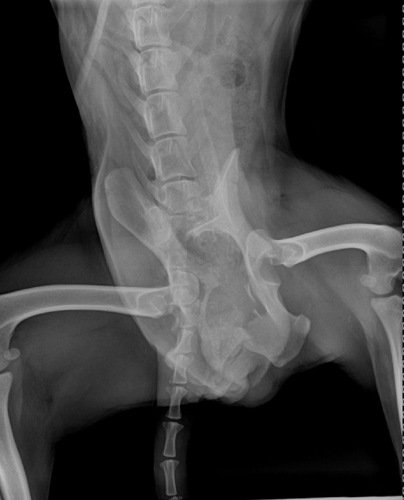

Doguinho foi atropelado na pista de engenheiro coelho, uma pessoa de bom coração conseguiu tirar ele da beirada da pista, porém não tem condições de pagar cirurgia e nem os medicamentos. Resgatamos ele e levamos até o consultório da Dra Daniela, onde foi feito um raio X que apontou várias fraturas. E será necessário realizar uma cirurgia pois ele está sofrendo muito. Toda ajuda é bem vinda, nos ajude a dar um recomeço lindo para esse doguinho ❤️